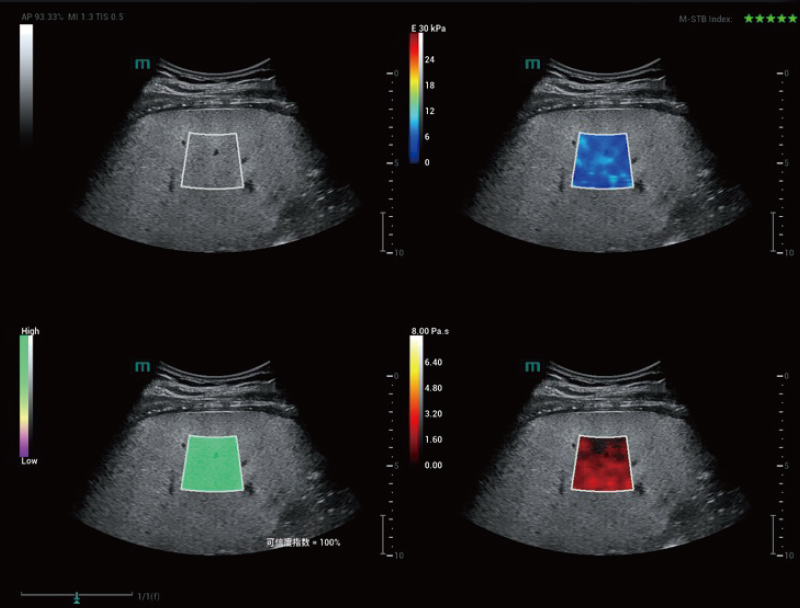

STVi maakt de kwantitatieve evaluatie van weefselviscositeit mogelijk en biedt realtime, multi-parametrische beeldvorming. Dit maakt een bredere benadering mogelijk van beeldvormingsdiagnose en kwantitatieve analyse van chronische leverziekten, borstlaesies en andere aandoeningen.

Dubbele kwantitatieve co?ffici?nten

Beoordeling van chronische leveraandoeningen

Meerdere kwantificeringstools

Beoordeling van borsttumoren